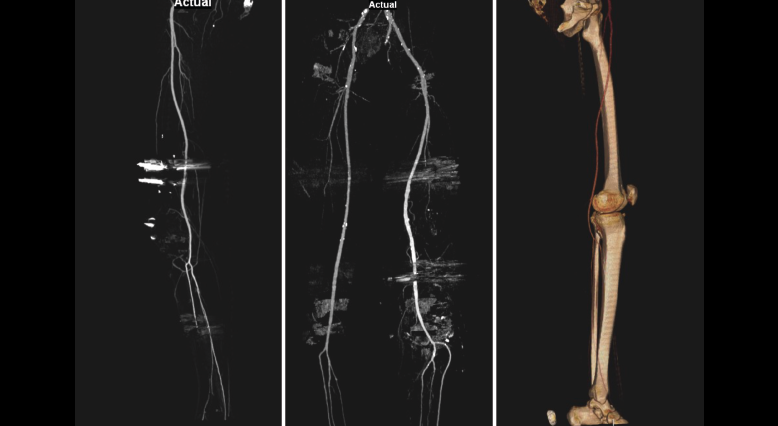

2.5. Afectación vascular

Aunque es rara la afectación de los vasos poplíteos, tanto en las fracturas como en las luxaciones, el estudio con angio-TAC permite el diagnóstico de estas lesiones. La afectación arterial es poco frecuente y la trombosis venosa profunda la lesión más común (Figura 25).

Figura 25. Reconstrucción MIP (proyección de máxima intensidad) de angio-TAC de miembros inferiores: son frecuentes los desplazamientos arteriales de los vasos comprimidos por los fragmentos de las fracturas como en la imagen central. Figura derecha: reconstrucción 3D.